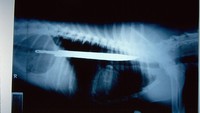

Dari Indonesia ada foto rontgen dari Orangutan Sumatera (Pongo abelii) yang memiliki 60 pelet senapan angin di jasadnya. Ngeri...